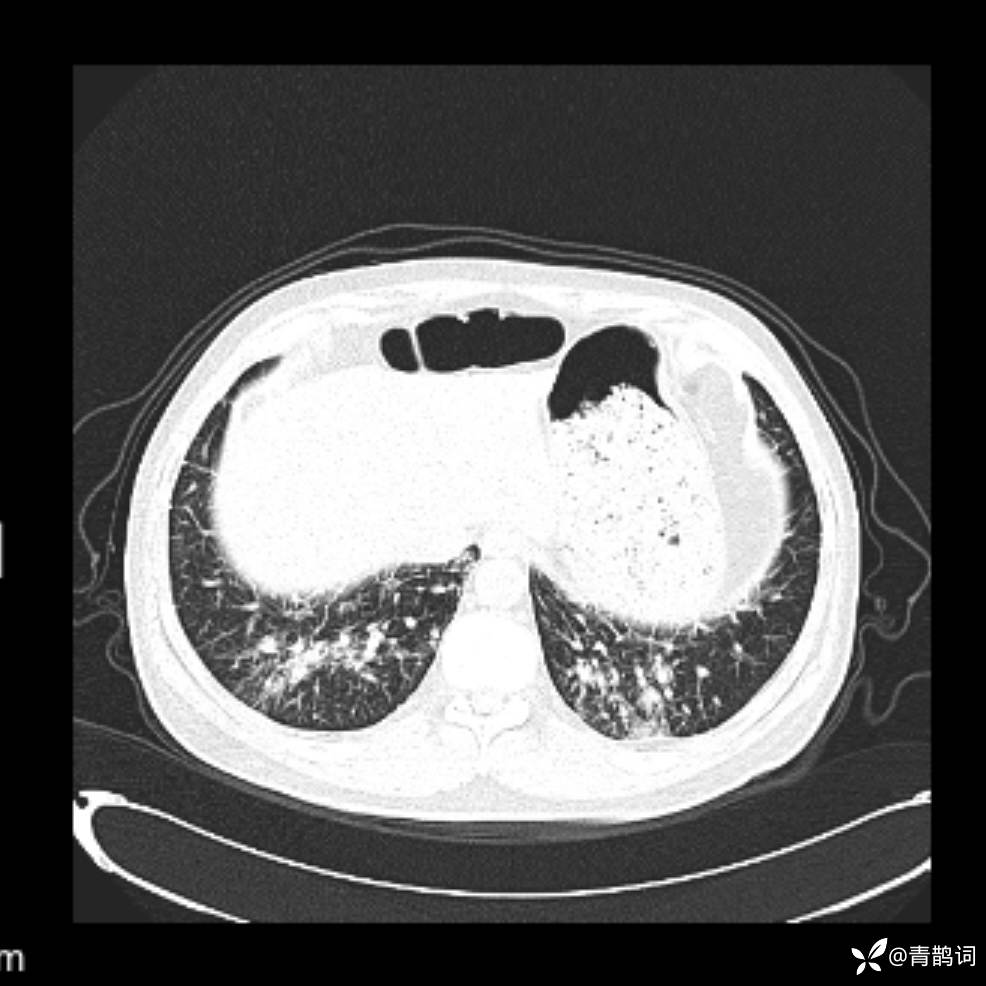

患者年龄:30岁。

患者性别:男。

简要病史:左颜面部肿胀2年,反复咳嗽咳痰,逐渐加重。

结合病史及影像学表现,期待评论区各位老师各抒己见~

木村病 (14)